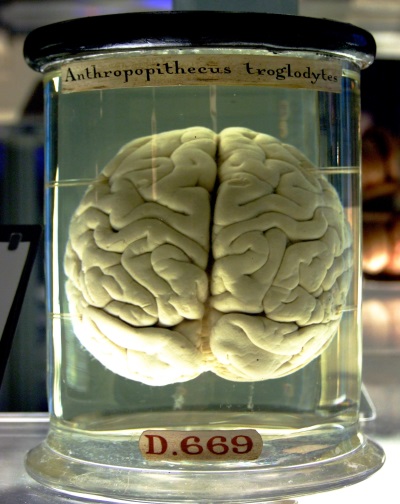

Az emberi agy - az egyik legtitokzatosabb emberi szervezetben. A tudósok még mindig nem teljesen értem a mechanizmus szellemi tevékenység, működésének tudatosság és.

Az evolúció során az emberi agy körül alakult ki egy erős koponya, védi a veszélyeztetett fizikai hatásait a szervezetben. Az agy tovább tart, mint 90% -át a helyet a koponya. Ez három fő részből áll: